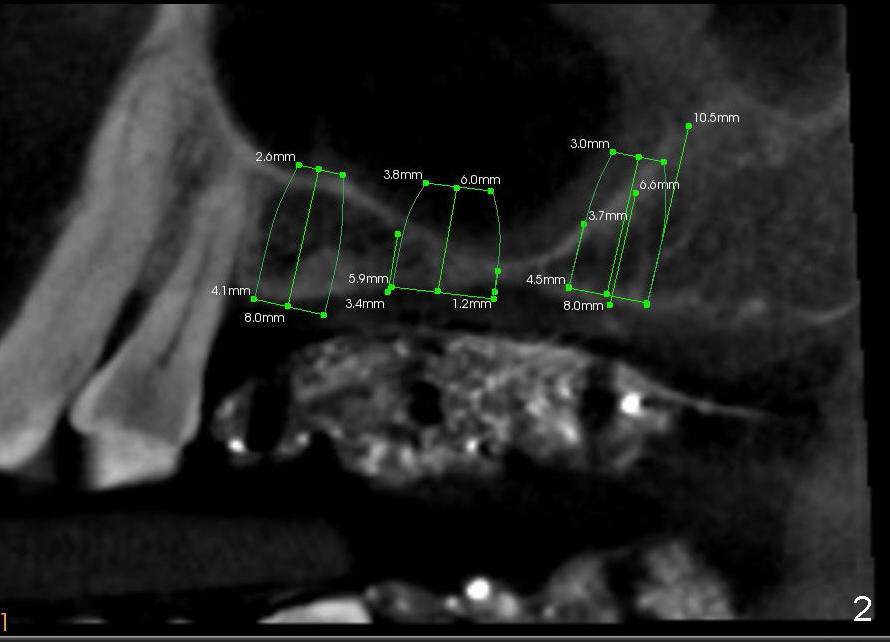

Davis has multiple missing teeth. We plan to place an implant at the site of #2, but he thinks that the tooth #31 is useless. Since there is an opposing tooth and implant placement at the site of #14 is challenging due to limited bone height (Fig.2: CT sagittal section), his first implant will be at the site of #13 (Fig.1-3). Two implant designs are gingiva- (Fig.1) and bone- (Fig.2,3 (coronal section) level.

CT analysis (Hounsfield units) shows D2/3 bone at the site of #13. Osteotomy is created by using drills. Fig.4 shows 3.5 mm drill at the depth of 8 mm. The trajectory needs to be adjusted. When 4 mm drill is done, the osteotomy is ovoid in shape. The implant should be 4 or 4.5 mm?